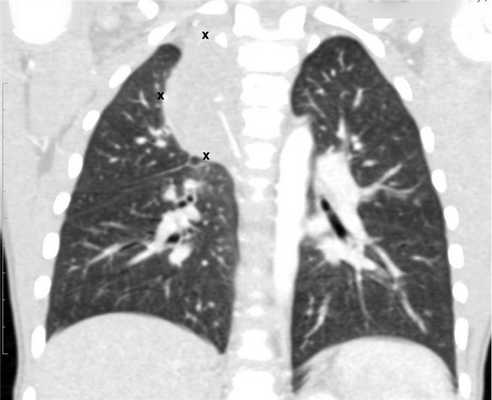

Рисунок 6. — КТ органов грудной клетки - семинома средостения.

- Рентгенография органов грудной клетки (данное обследование обязательно, потому что оно дает возможность подтвердить диагноз при первичных новообразованиях средостения и наличии метастазов в легких).

- КТ (расшифровка: компьютерная томография), МРТ (расшифровка: магнитно-резонансная томография), ПЭТ-КТ (расшифровка: позитронно-эмиссионная томография, совмещенная с КТ). Эти обследования необходимы, чтобы рассмотреть структуры организма послойно и визуализировать опухоль. Они показывают, как сильно распространен патологический опухолевый процесс на находящиеся рядом ткани и органы, есть ли поражение костей. КТ - это самый чувствительный метод для обнаружения метастазов в легких. Проведение МРТ и КТ головного мозга необходимо, чтобы обнаружить и визуализировать герминогенные новообразования эпифиза.

![Метастазы в легких до лечения и после 4х циклов химиотерапии по схеме «ВЕР» (КТ грудной клетки)]()

Метастазы в легких до лечения и после 4х циклов химиотерапии по схеме «ВЕР» (КТ грудной клетки)